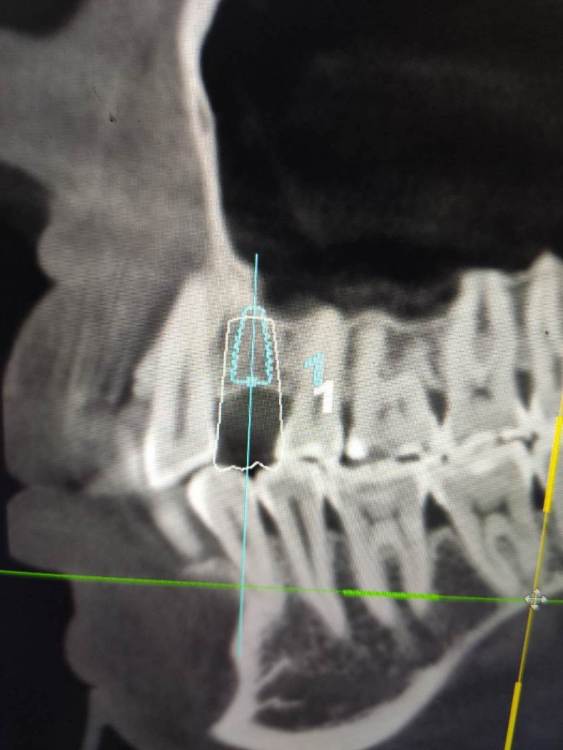

Irouil Опубликовано 4 мая, 2021 Поделиться Опубликовано 4 мая, 2021 (изменено) Тут стучать вообще не обязательно, просто пилотным сверлиться и экспандером расшириться. Если исходит из этого положения винта а если пойти ортодоксальнее и сместить его дистальнее, то ничего там при стуке не отломается Изменено 4 мая, 2021 пользователем Irouil Ссылка на комментарий

АнтонТЛТ Опубликовано 4 мая, 2021 Поделиться Опубликовано 4 мая, 2021 4.0*7.3 синус не нужен, нужна нкр Ссылка на комментарий

Irouil Опубликовано 4 мая, 2021 Поделиться Опубликовано 4 мая, 2021 (изменено) Не очень понял, что не так в предложенном автором вопроса варианте расстановки и зачем переходить на вариант с НКР и винтом 4.0? Изменено 4 мая, 2021 пользователем Irouil Ссылка на комментарий

АнтонТЛТ Опубликовано 4 мая, 2021 Поделиться Опубликовано 4 мая, 2021 Винт 4.0 потому что в данной системе, которую я поставил он 7.3мм, диаметром 3.5 только 8.5мм и более. У автора 3.6 на 7мм как я понял) Автор установил имплантат очень глубоко, чтобы избежать нкр и близко к клыка. Какой будет профиль прорезывания и что будет с костным пиком через несколько месяцев после протезирования? Ссылка на комментарий

Irouil Опубликовано 4 мая, 2021 Поделиться Опубликовано 4 мая, 2021 У меня нет дома просмотрщика с модельками, поэтому скриншотов не будет, но в целом соглашусь - нужно НКР. И вертикальный синус) Правда НКР несложная, дефект практически трехстеночный. На уровне платформы больше 3.5 мм не вижу ширину гребня Ссылка на комментарий

Женька Опубликовано 5 мая, 2021 Поделиться Опубликовано 5 мая, 2021 @АнтонТЛТ неа, 3.5*8 Можно конечно вариант который я ранее предлагал 7мм винт из которых 1.5мм полированная шейка. Но с НКР её(шейку) не совместить я так понимаю. Ссылка на комментарий